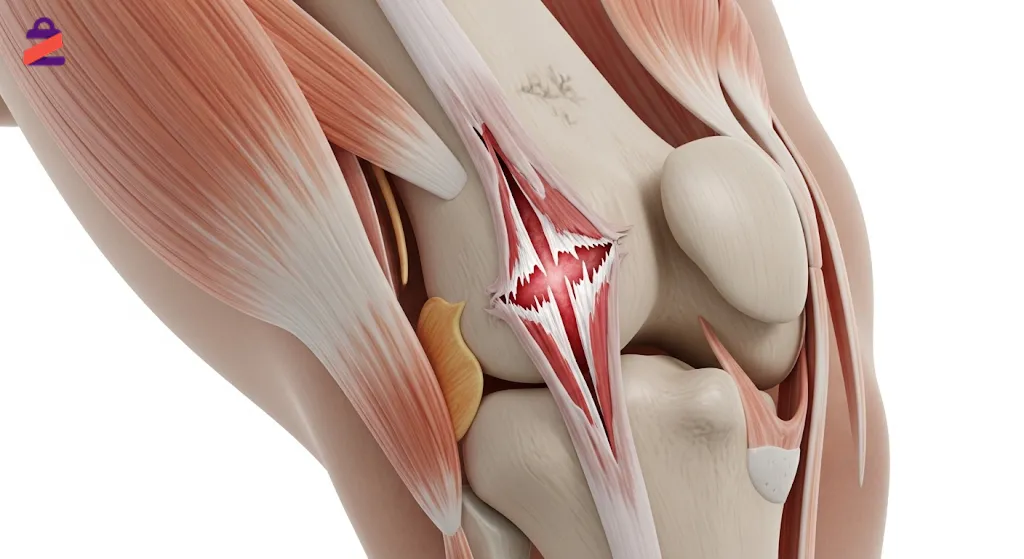

پارگی تاندون زانو چیست؟

پاره شدن تاندون زانو زمانی رخ میدهد که بافت فیبری محکمی که عضلات ران را به استخوان پاتلا (کشکک زانو) متصل میکند، دچار آسیب شدید یا گسستگی شود.

این تاندون نقش مهمی در صاف کردن پا و انجام حرکاتی مانند راه رفتن، دویدن و پریدن دارد. پارگی ممکن است بهصورت کامل یا ناقص اتفاق بیفتد و شدت آن به میزان آسیب و محل گسستگی بستگی دارد.

در بسیاری از موارد، این مشکل بر اثر ضربه مستقیم، فرود نادرست پس از پرش یا فشار ناگهانی بر مفصل زانو ایجاد میشود. تشخیص بهموقع و شروع درمان مناسب، از گسترش آسیب و نیاز به جراحیهای پیچیده جلوگیری میکند.

پاتلا زانو چیست و تاندون پاتلار چه نقشی دارد؟

پاتلا یا کشکک زانو یک استخوان کوچک، مثلثیشکل و متحرک است که در جلوی مفصل زانو قرار دارد و مانند یک سپر از ساختارهای داخلی زانو محافظت میکند.

این استخوان توسط تاندون پاتلار به استخوان ساق پا (تیبیا) متصل میشود و نقش کلیدی در انتقال نیروی عضلات ران به ساق پا برای صاف کردن زانو دارد.

تاندون پاتلار در حرکاتی مانند ایستادن، بالا رفتن از پله، دویدن و پریدن نقش حیاتی ایفا میکند و هرگونه آسیب به آن میتواند عملکرد کلی پا را مختل کند.